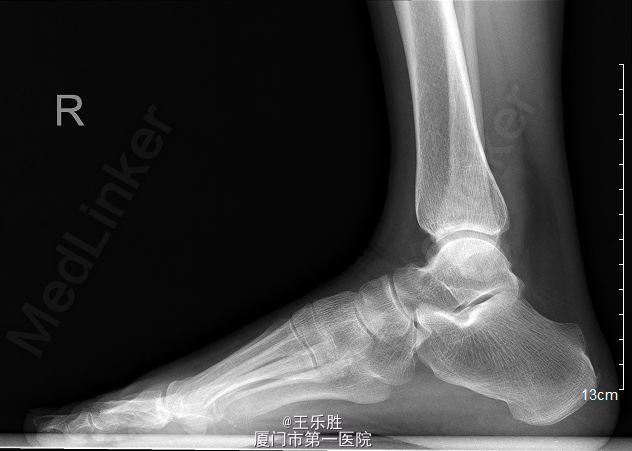

患者,女,58岁,因“右足跖趾关节酸痛半年”入院。

右足第一跖趾关节前侧可见红肿,关节处无明显压痛,关节活动尚可,足背动脉可及,足趾伸屈正常。远端血循良好,感觉正常。我院 MRI示右足第1跖趾关节积液,滑膜炎考虑。

初步诊断:右足第一跖趾关节滑膜炎.行“右第1跖趾关节滑膜切除+关节清理+骨赘切除术 ”.